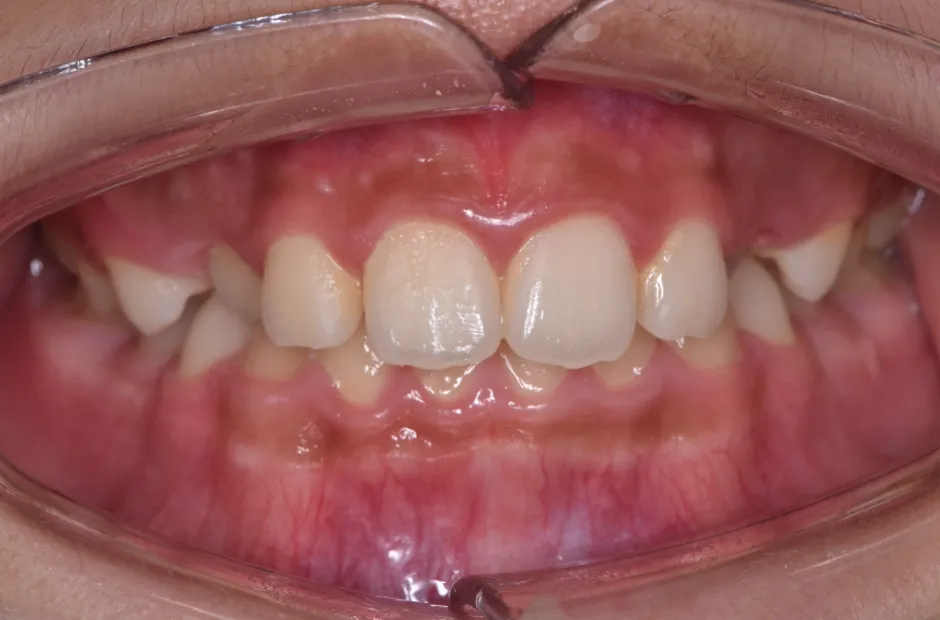

先天欠如

| 診断名・主訴 | 先天欠如 |

|---|---|

| 年齢・性別 | 14歳・女性 |

| 治療期間・回数 | 2年 |

| 治療に用いた主な装置 | ブラケット矯正 |

| 抜歯部位 | なし |

| 治療費 | 60万円(税抜) |

| リスク・副作用 | 装置による違和感・疼痛・歯肉退縮・歯根吸収・虫歯のリスクなど |